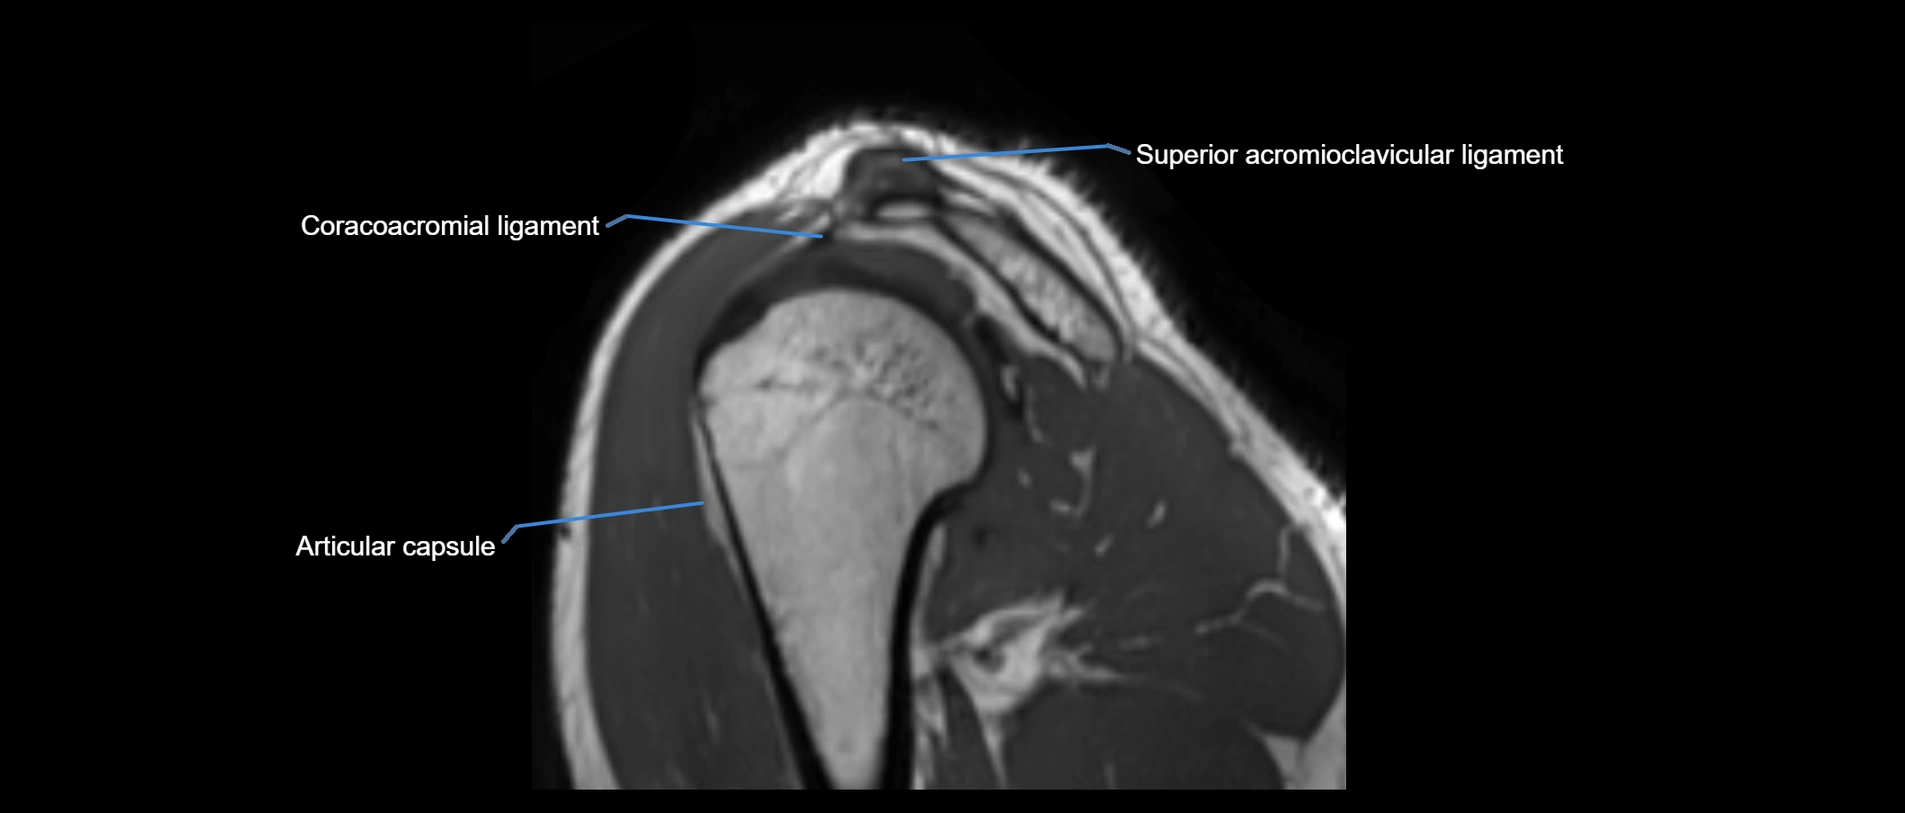

MRI images

image

MRI Appearance

• T1-weighted images:

• Normal ligament: Low signal (dark linear band) spanning acromion to clavicle.

• Surrounding fat planes: Bright, delineating the ligament clearly.

• Marrow of clavicle and acromion: Bright due to fatty content.

• Tears: Discontinuity or irregular thickening with intermediate-to-bright signal.

• Chronic injury: Thinning, fraying, or irregular low-signal fibers with adjacent scarring.

• T2-weighted images:

• Normal ligament: Low signal, homogeneous.

• Partial tear or sprain: Focal hyperintensity or thickening.

• Complete tear: Discontinuity with fluid-bright gap between clavicle and acromion.

• Associated edema: Bright signal in distal clavicle or acromion marrow.